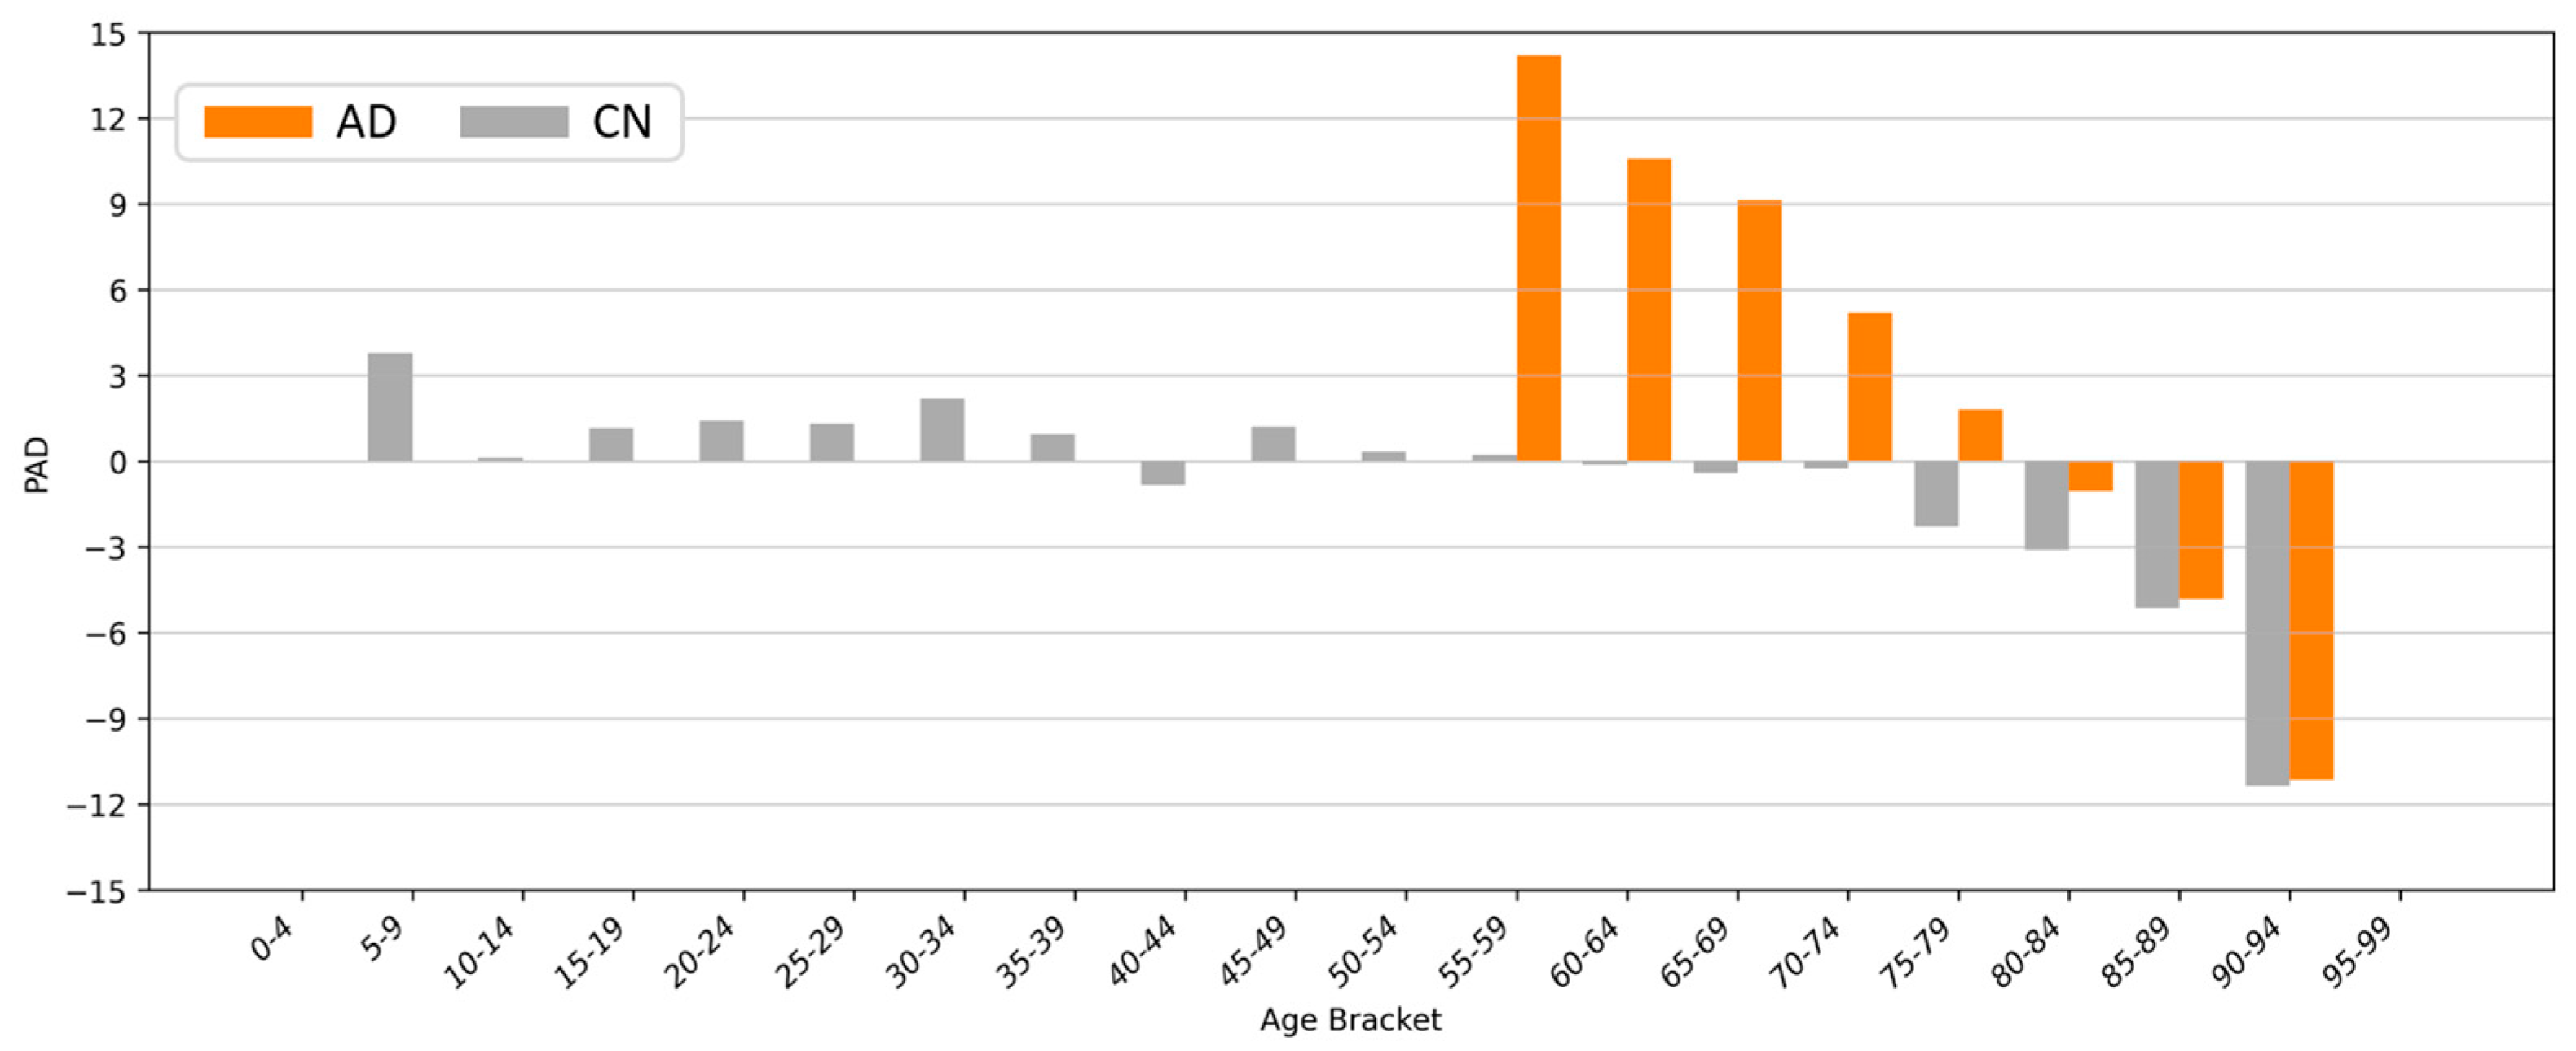

4.5. Clinical Applications and Efficacy Assessment